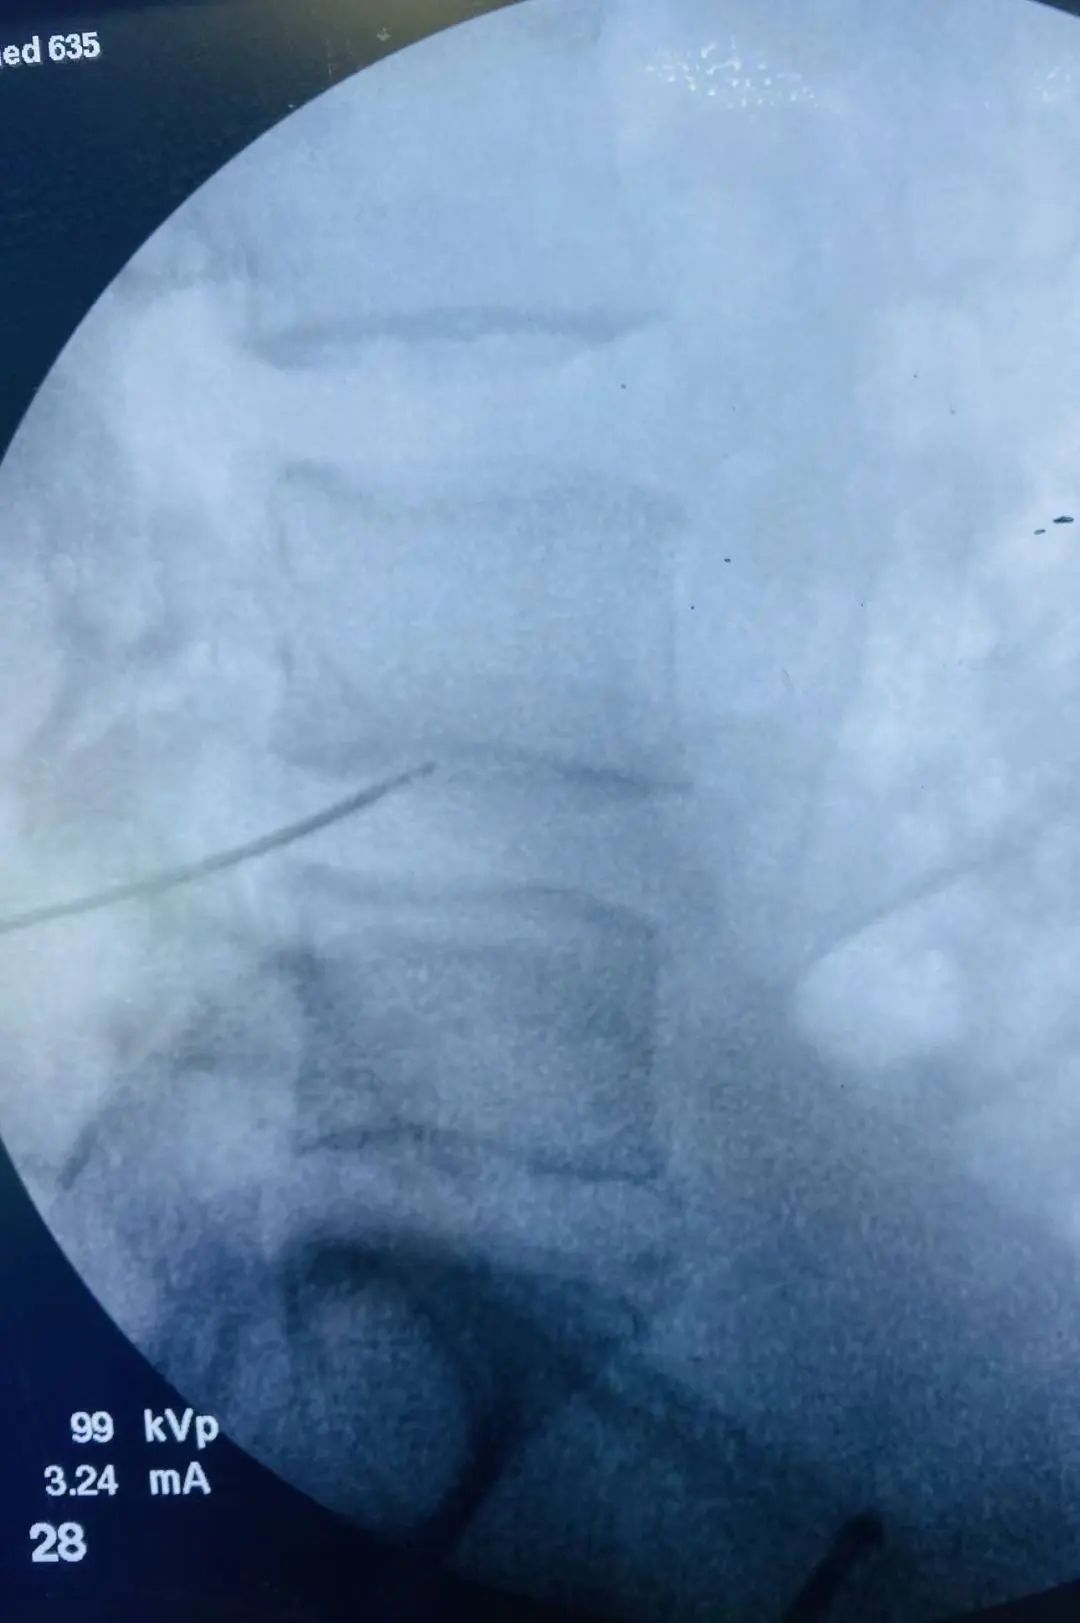

于6月9日在手术麻醉科配合下,脊柱外科管廷进主任医师、孙鹏副主任医师、苏凯主治医师在局部麻醉下为患者实施L4/5椎间盘低温等离子射频消融、椎间盘汽化微创手术,手术顺利,术后患者腰腿痛不适症状即刻缓解。

低温等离子射频消融术的原理是通过等离子刀将射频能量作用于椎间盘内部,汽化消融部分椎间盘髓核组织,然后再利用精确的热皱缩技术将刀头接触到的髓核组织加温至约70度,使髓核体积缩小,降低椎间盘内压力,从而缓解椎间盘突出对神经根的压迫而达到治疗的目的。

低温等离子射频消融术的优点:1.安全性高:等离子工作温度在40-70度,低温安全,不开刀创伤小、最大限度保护纤维环壁,不破坏正常椎间盘;术中对骨性结构无破坏,对脊柱稳定性影响小。2.创伤小,术中几乎不出血,局部皮肤只有1mm针孔疤痕,不影响美观,恢复快,术后2-3天即可下床活动出院。